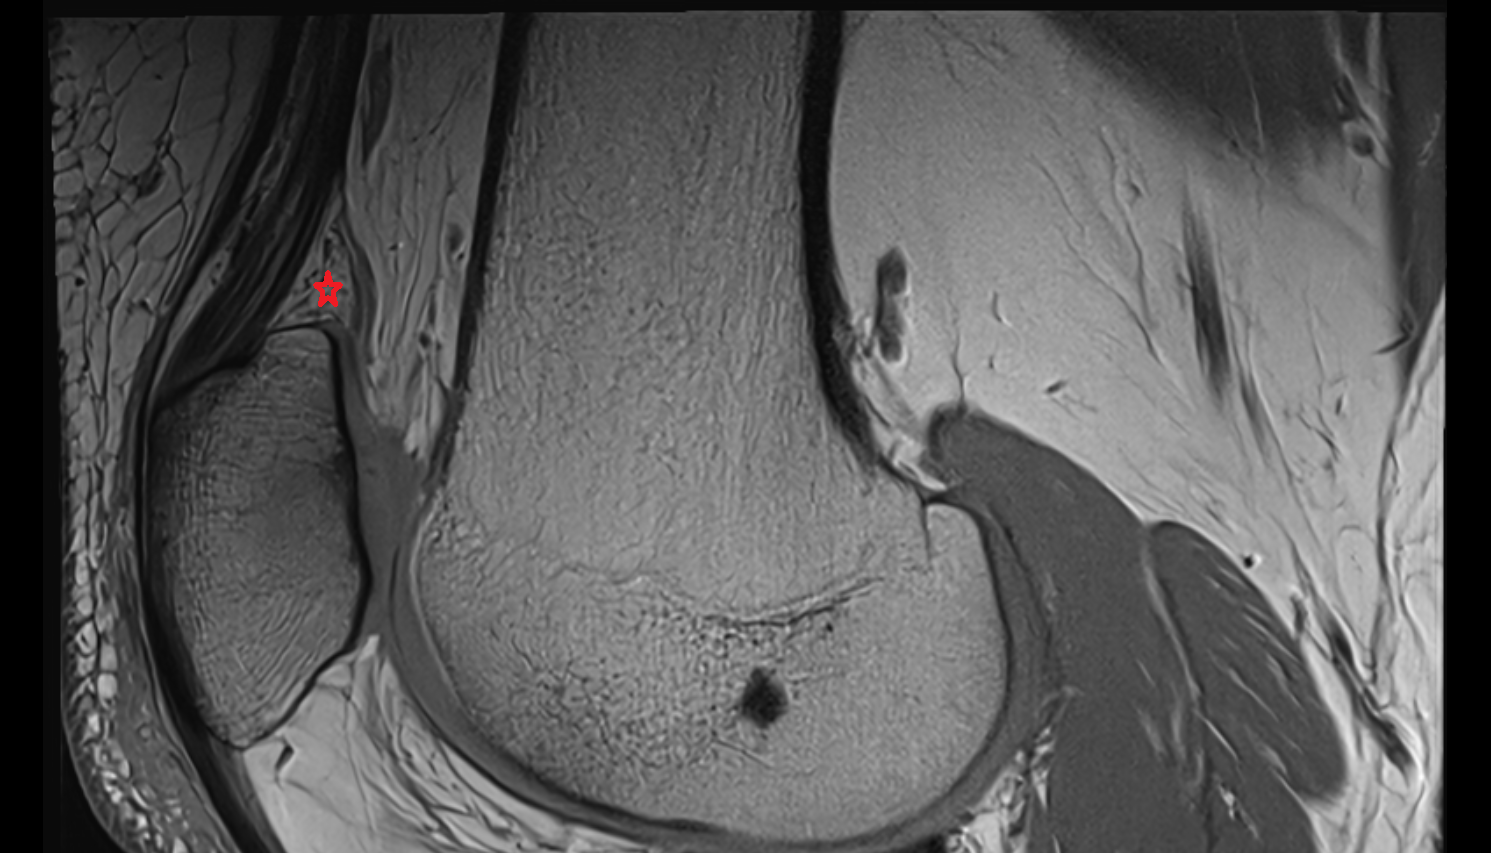

- Meniscus cartilage

- Medial meniscus

- Lateral meniscus

- Anterior horn of medial meniscus

- Posterior horn of medial meniscus

- Body of medial meniscus

- Anterior root of medial meniscus

- Posterior root of medial meniscus

- Anterior horn of lateral meniscus

- Posterior horn of lateral meniscus

- Body of lateral meniscus

- Anterior root of lateral meniscus

- Posterior root of lateral meniscus